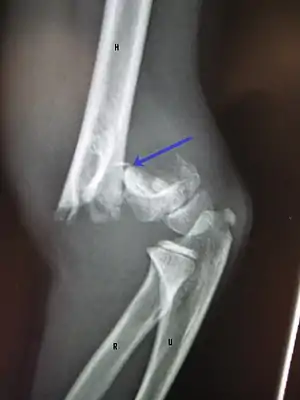

Distal humeral fracture

A displaced supracondylar fracture in a child